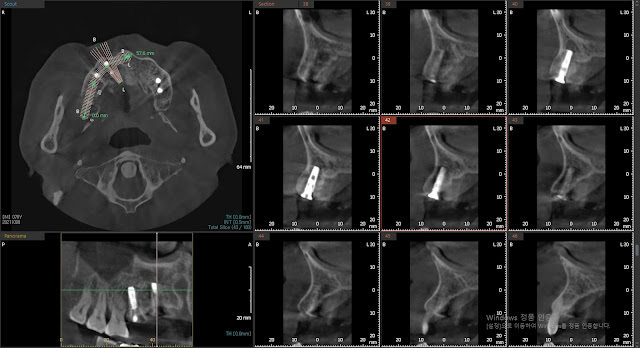

The patient is a 79-year-old male who came for dental treatment due to fractured teeth in the maxilla at tooth numbers 13 and 15. The radiograph provided is an image taken before the fracture occurred.

Based on the CT findings before the fracture, tooth number 13 showed a position toward the contralateral side.

This is the picture showing the position of the implant at tooth number 13. The position is appropriate, and the implant is not exposed, showing a healing appearance.

Radiographic results.